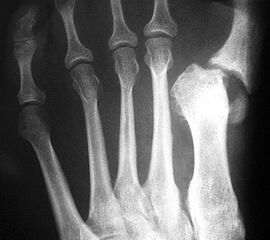

Die dorsoplantaren Röntgenaufnahmen zeigen eine Open-wedge Technik mit der normalerweise ein erhöhter intermetatarsaler Winkel gut zu korrigieren ist (Abbildung 3). Die Wirksamkeit einer Basisosteotomie ist umso größer, je proximaler diese durchgeführt wird. Je weiter distal die Osteotomie, umso geringer die Korrektur. Auf den postoperativen Bildern ist der distal unverändert große Abstand zwischen Metatarsale I und Metatarsale II erkennbar, bei gleichzeitiger Subluxation des Großzehengrundgelenks und dezentrierten Sesambeinen. Darüber hinaus finden sich initiale degenerative Veränderungen im Großzehengrundgelenk. Klinisch bestand eine hohe Weichteilspannung, bei verkürzter Extensor- und Flexor hallucis longus Sehne.  Daher wurde ein verkürzendes Verfahren zur Revision gewählt (Abbildung 4). Die Lapidusarthrodese stellt ein sehr zuverlässiges Verfahren zur Behandlung von Hallux valgus Rezidiven dar 9. Die Fusion des Tarsometatarsale-I-Gelenks kombiniert Stabilität mit einem hohen Korrekturpotenzial. Aufgrund der verfahrensimmanenten Verkürzung des ersten Strahls und der in diesem Fall bereits präoperativ vorhandenen Transfermetatarsalgie wurde die Entscheidung für eine verkürzte Weil-Osteotomie am zweiten bis fünften Strahl gefällt. Die Kombination beider Verfahren führte zu einem homogenen Metatarsale-Index und zu einer gleichmäßigen plantaren Druckverteilung 10. Die Hallux valgus interphalangeus Fehlstellung wurde mit einer Akin-Osteotomie korrigiert.